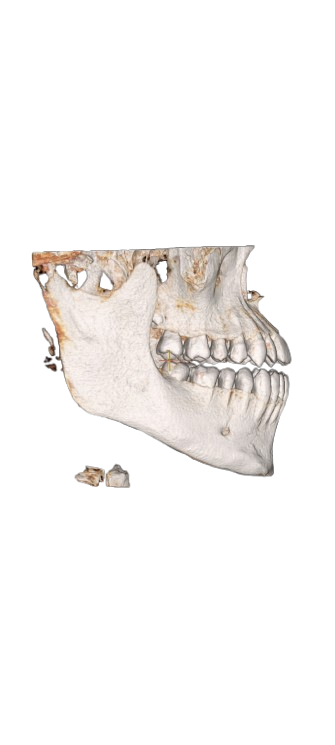

My maxillofacial surgeon said there are no problems and the solution depends on the bite and teeth

Screenshot_2026-03-12-20-45-14-649_com.openai.chatgpt-removebg-preview.png115.2 KB · Views: 0

Screenshot_2026-03-12-20-45-14-649_com.openai.chatgpt-removebg-preview.png115.2 KB · Views: 0 -